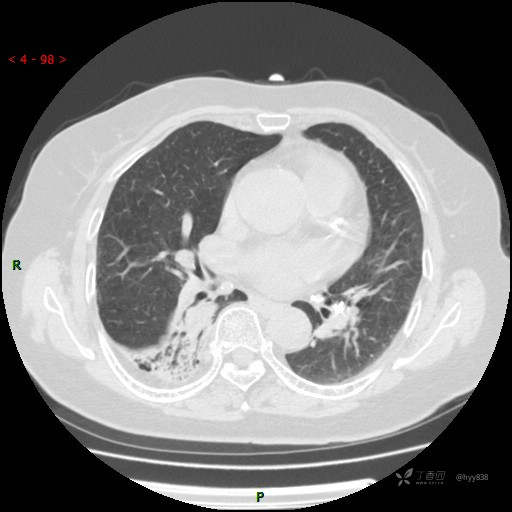

增强动脉期